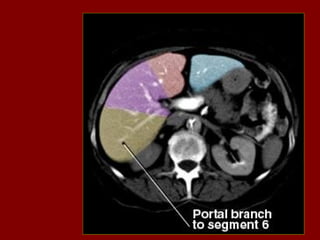

INCISÃO SOBRA AVEIA HEPÁTICA DIREITA

INCISÃO SOBRE AVEIA HEPÁTICA MÉDIA.

INCISÃO SOBRE AVEIA HEPÁTICA ESQUERDA.